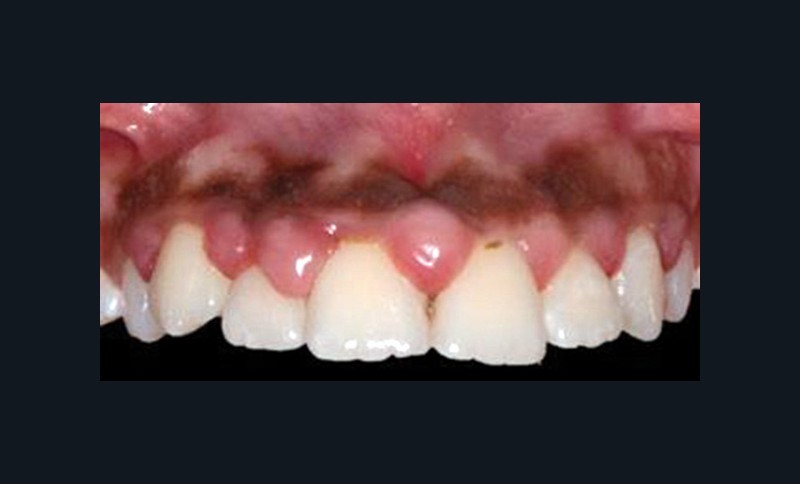

La parodontite chronique est une maladie inflammatoire d’origine bactérienne, dont la prévalence est très élevée. Bien que les progrès des thérapeutiques soient nombreux et concernent un nombre important de traitements parodontaux, la thérapeutique étiologique non chirurgicale reste le traitement initial de choix des parodontites. Elle comprend un enseignement à l’hygiène orale et un débridement mécanique du biofilm bactérien, à l’aide d’ultrasons ou de curettes. L’antibiothérapie systémique n’est pas systématique, mais est indiquée dans les cas les plus sévères. Souvent, la seule thérapie mécanique se montre efficace et suffisante pour obtenir des améliorations cliniques très significatives. Cependant, elle a aussi des limites, et certains sites d’accès délicats nécessitent alors une thérapeutique chirurgicale complémentaire. Enfin, la stabilisation de la situation à long terme ne peut être obtenue que si une maintenance rigoureuse et régulière est mise en place(fig. 5 et 6).